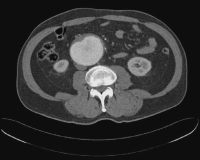

Abbildung 1: CT-Scan mit Kontrastmittelinjektion: Voluminöses abdominelles Aortenaneurysma mit einem muralen Thrombus.

Keywords:

Aortenaneurysma

,

CT-Scan

Hypertonie

muraler Trombus